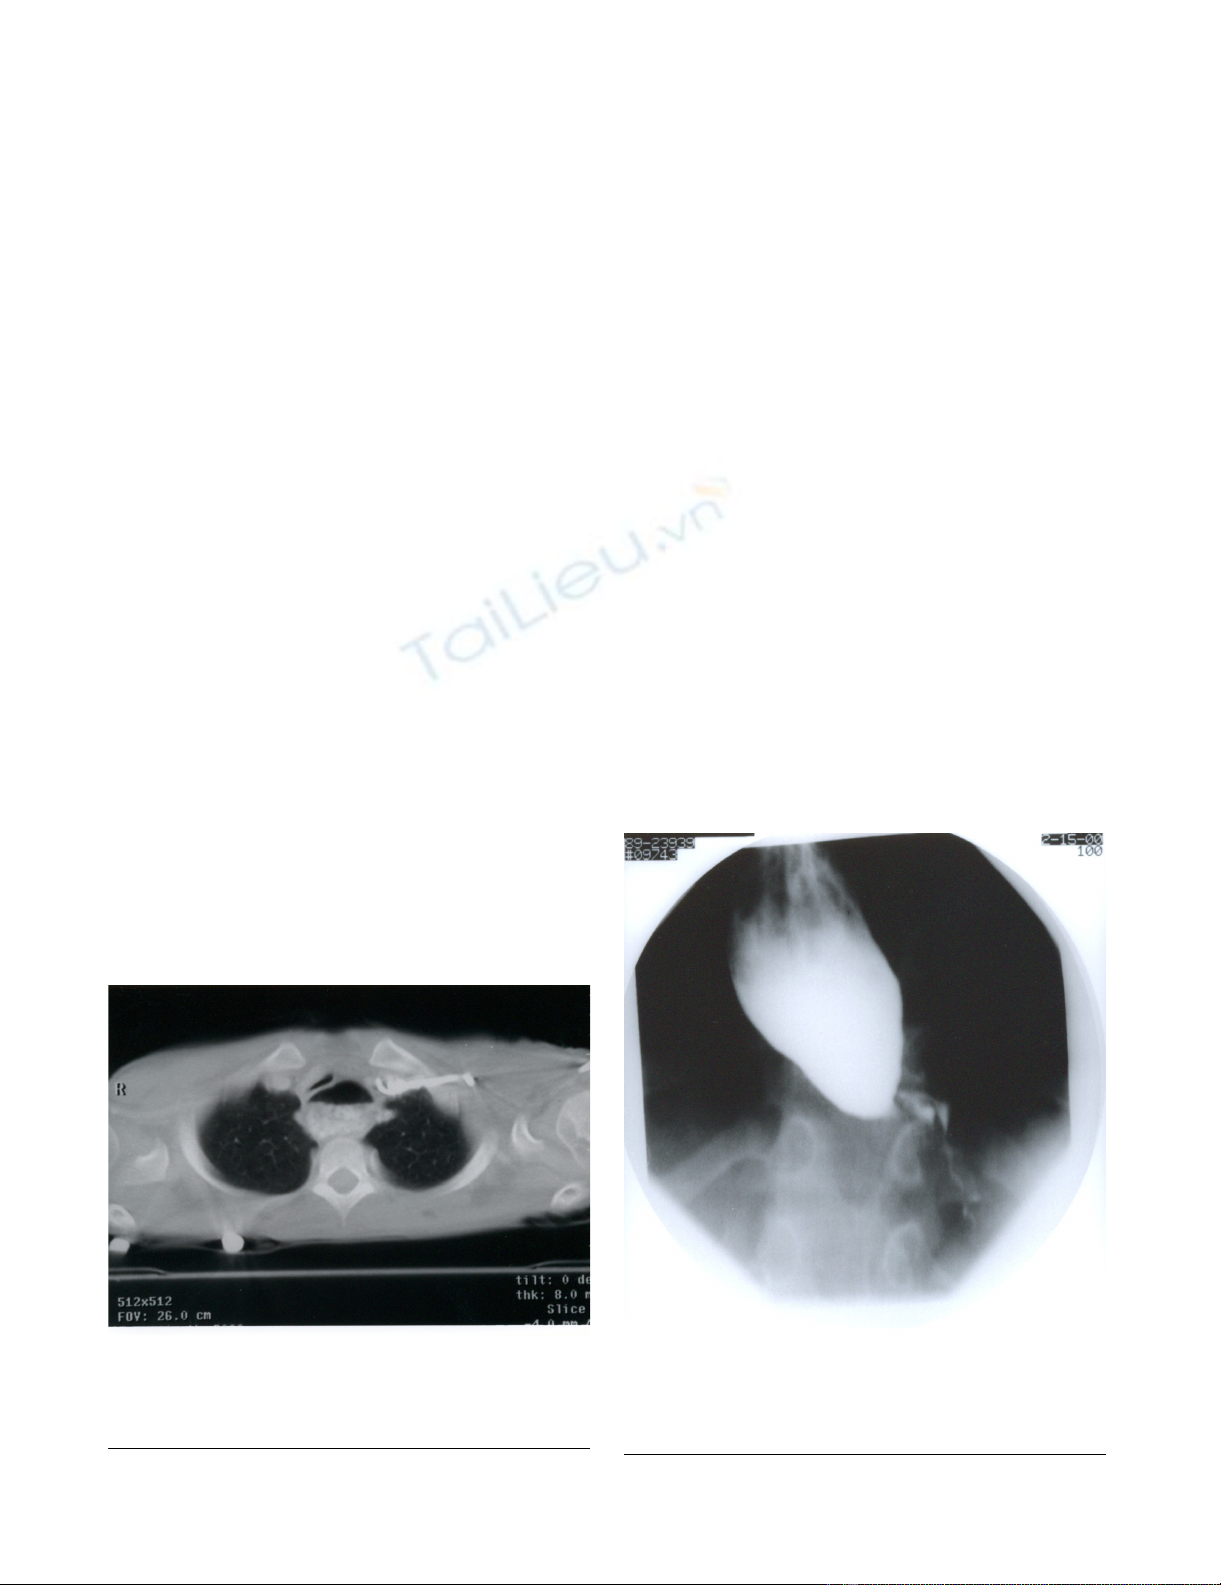

Because of the mid tracheal collapse observed during

bronchoscopy, a cine-CT with contrast was done to rule

out vascular ring with compression of the trachea. The CT

showed no abnormal vasculature but did show a large

dilated esophagus with air-fluid level from stagnant food

material (Figure 1). The trachea was compressed by the

dilated esophagus and deviated towards the right. A Bar-

CT scan of chest showing dilatation of esophagus with air-fluid levelFigure 1

CT scan of chest showing dilatation of esophagus

with air-fluid level. Dilated esophagus is compressing the

trachea anteriorly.